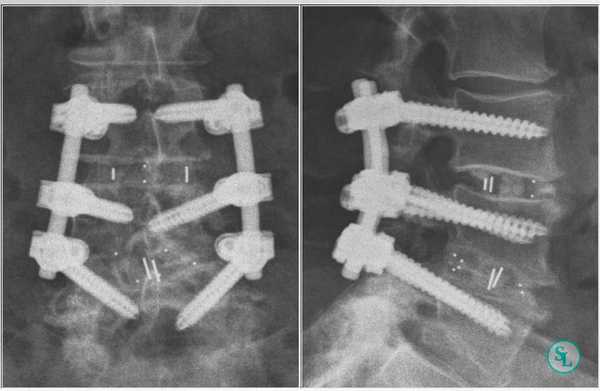

Транспедикулярная фиксация позвоночника

Транспедикулярная фиксация или ТПФ - операция, при которой позвонки фиксируются и стабилизируются при помощи специальных имплантов (транспедикулярных винтов). В каждом позвонке есть точка ввода винта, которую установил в 1985 году Рой Камилл — это точка пересечения поперечного отростка позвонка с верхнем суставным отростком. С помощью специальных инструментов в эту точку, вкручиваются винты определяя анатомически правильное расположение позвоночника, тем самым излечивая заболевание. Первые попытки установки имплантов были в 60-70 гг. прошлого века и с тех пор является «золотым стандартом» в лечения переломов и различных заболеваний позвоночника.

ТПФ выполняется под рентгеновским контролем, что позволяет хирургу точно контролировать каждое движение и избежать повреждения близкорасположенных анатомических структур. Чаще для этого используется ЭОП или КТ.

Очень важно при установки винтов соблюсти следующие моменты: отсутствие пространства между костью и винтом, исключение травматизации нервных и сосудистых структур или смежных дугоотросчатых суставов. Импланты устанавливаются согласно размерной линейки каждого позвонка и винта, бикортикально не касаясь замыкательных пластин.

Безусловно, предельно качественное выполнение ТПФ обеспечивается при применении устройств 3-го поколения. Современные имплантируемые кейджи позволяют надежно зафиксировать патологически измененный сегмент позвоночника и устранить болевой синдром, обусловленный его остаточной подвижностью.

Размер закрепляющих винтов для каждого больного подбирается индивидуально. Различают моноаксиальные и полиаксиальные винты, также разработаны варианты с боковой фиксацией стержня. Они вводятся по конвергентной монокортикальной методике, подразумевающей перфорацию позвонка только в точке входа винта.

Винты изготавливаются из титана, что гарантирует их высокую стойкость к различным деформирующим нагрузкам. Они оснащены поверхностными колпаками, обеспечивающими стабильность положения конструкции и ее защиту от перекоса. Все винты установленной системы объединяются специальными пружинистыми металлическими механизмами, что равномерно перераспределяет нагрузку на них.

Точка установки винта в корень дуги подбирается на основании расположения двух анатомических ориентиров - поперечного и суставного отростков позвонка. Непосредственно позвонок перфорируют с помощью специального зонда.

Нестабильность позвоночника считается одним из распространенных заболеваний и основным методом лечения является транспедикулярная фиксация подвижного сегмента, декомпрессивная ляминэктомия, дискэктомия с установкой между телами позвонков кейджа который фиксирует сегмент на 360 градусов (золотой стандарт). В подобных ситуациях метод обеспечивает надежный спондилодез у 80- 95% пациентов. ТПФ является одним из наиболее часто применяемых методов оперативного лечения заболеваний и травм в связи с тем, что современные хирурги стараются добиться спондилодеза на 360°. Достичь этого позволяет сочетание ТПФ с межтеловым спондилодезом, что обеспечивает высокую частоту костных сращений и отсутствие остаточной незначительной подвижности в передних отделах прооперированного сегмента. Поэтому при успешном завершении операции и правильном восстановлении пациенты гарантировано избавляются от болевого синдрома.